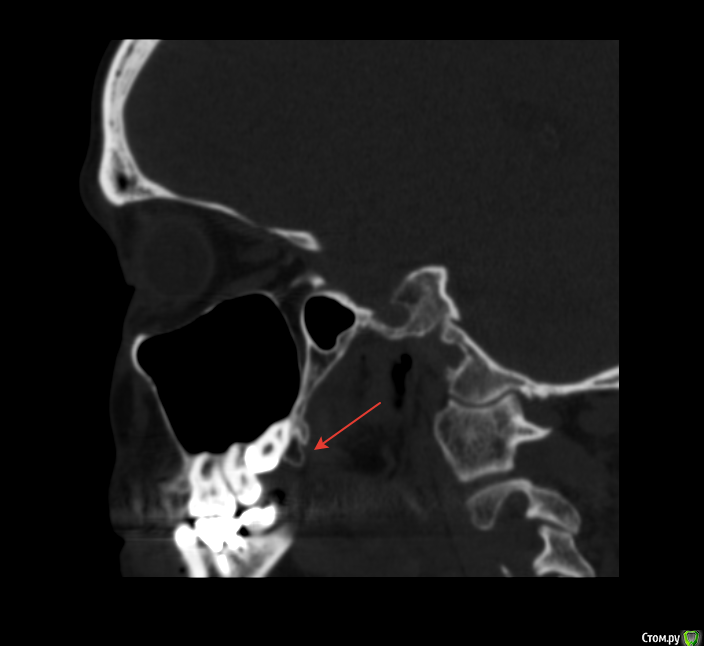

Снежана10 Опубликовано 30 августа, 2017 Автор Поделиться Опубликовано 30 августа, 2017 это я понимаю, а этот мешок на КТ это что? Ссылка на комментарий

red_butler Опубликовано 30 августа, 2017 Поделиться Опубликовано 30 августа, 2017 это я понимаю, а этот мешок на КТ это что?бугор верхней челюсти, кость это 1 Ссылка на комментарий